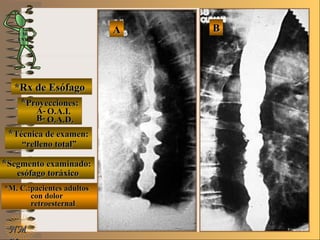

*Rx de Esófago*Rx de Esófago

**Proyecciones:Proyecciones:

**Técnica de examen:Técnica de examen:

**Segmento examinado:Segmento examinado:

*M. C.:paciente adulto con*M. C.:paciente adulto con

dolor retroesternaldolor retroesternal

O.A.D.O.A.D.

““mucosografía”mucosografía”

esófago toráxicoesófago toráxico